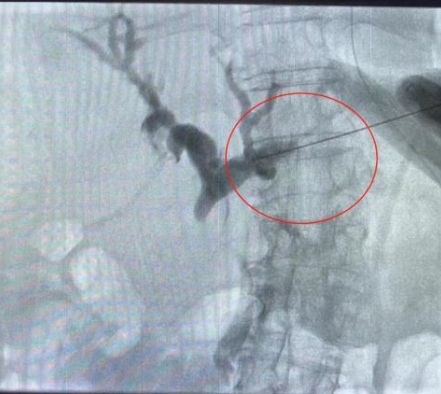

由于患者肝右葉占位巨大,完全遮擋右側(cè)穿刺路徑,左肝管為唯一穿刺路徑。介入科彭鵬醫(yī)生與重癥醫(yī)學科討論后,征得患者家屬同意后,擬行左側(cè)經(jīng)皮肝內(nèi)膽管穿刺引流術(shù)。術(shù)中一針便成功進入膽道系統(tǒng),導絲引流管放置順利,造影顯示膽道系統(tǒng)顯影滿意,側(cè)孔位置可,引流順暢,37分鐘便結(jié)束了手術(shù),術(shù)后順利轉(zhuǎn)入普外科護理治療。這例手術(shù)的成功開展,刷新了該院介入團隊高齡患者手術(shù)的新記錄!

經(jīng)皮肝內(nèi)膽管穿刺引流術(shù)是在醫(yī)學影像的引導下,利用穿刺針經(jīng)皮穿入肝內(nèi)膽管,注入對比劑,使肝內(nèi)外膽管迅速顯影后,置管引流以緩解梗阻癥狀。對于惡性梗阻性黃疸患者,通過該方式可降低血清膽紅素,有助于恢復肝腎功能,提高其生存質(zhì)量,延長生存期,部分患者還可獲得進一步治療的機會。對于良性梗阻性黃疸患者,除有利于迅速緩解黃疸和感染等癥狀外,還可為后續(xù)治療提供通道。